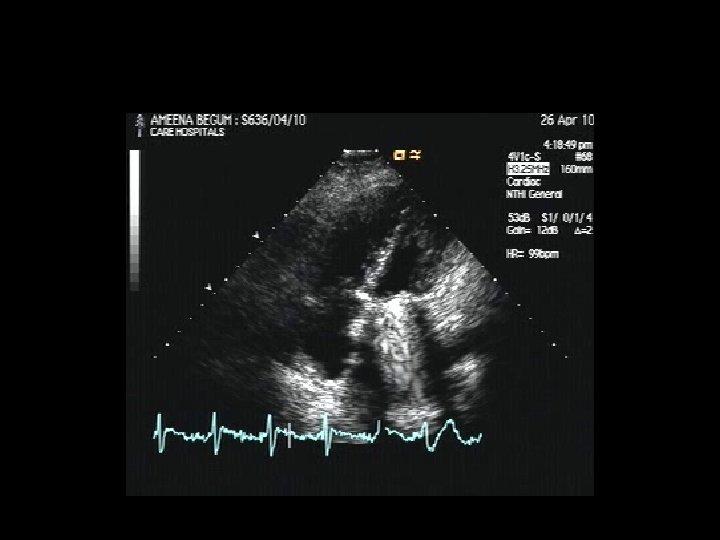

AMEENA BEGUM YRS F 32 MVR 3 YRS POST OP M-H VALVE INTERMITTENT ALTERNATE CYCLE JAMMED PRO VALVE ABSOLUTE EOSINOPHIL COUNT 720 mm 3 INR 5. 6